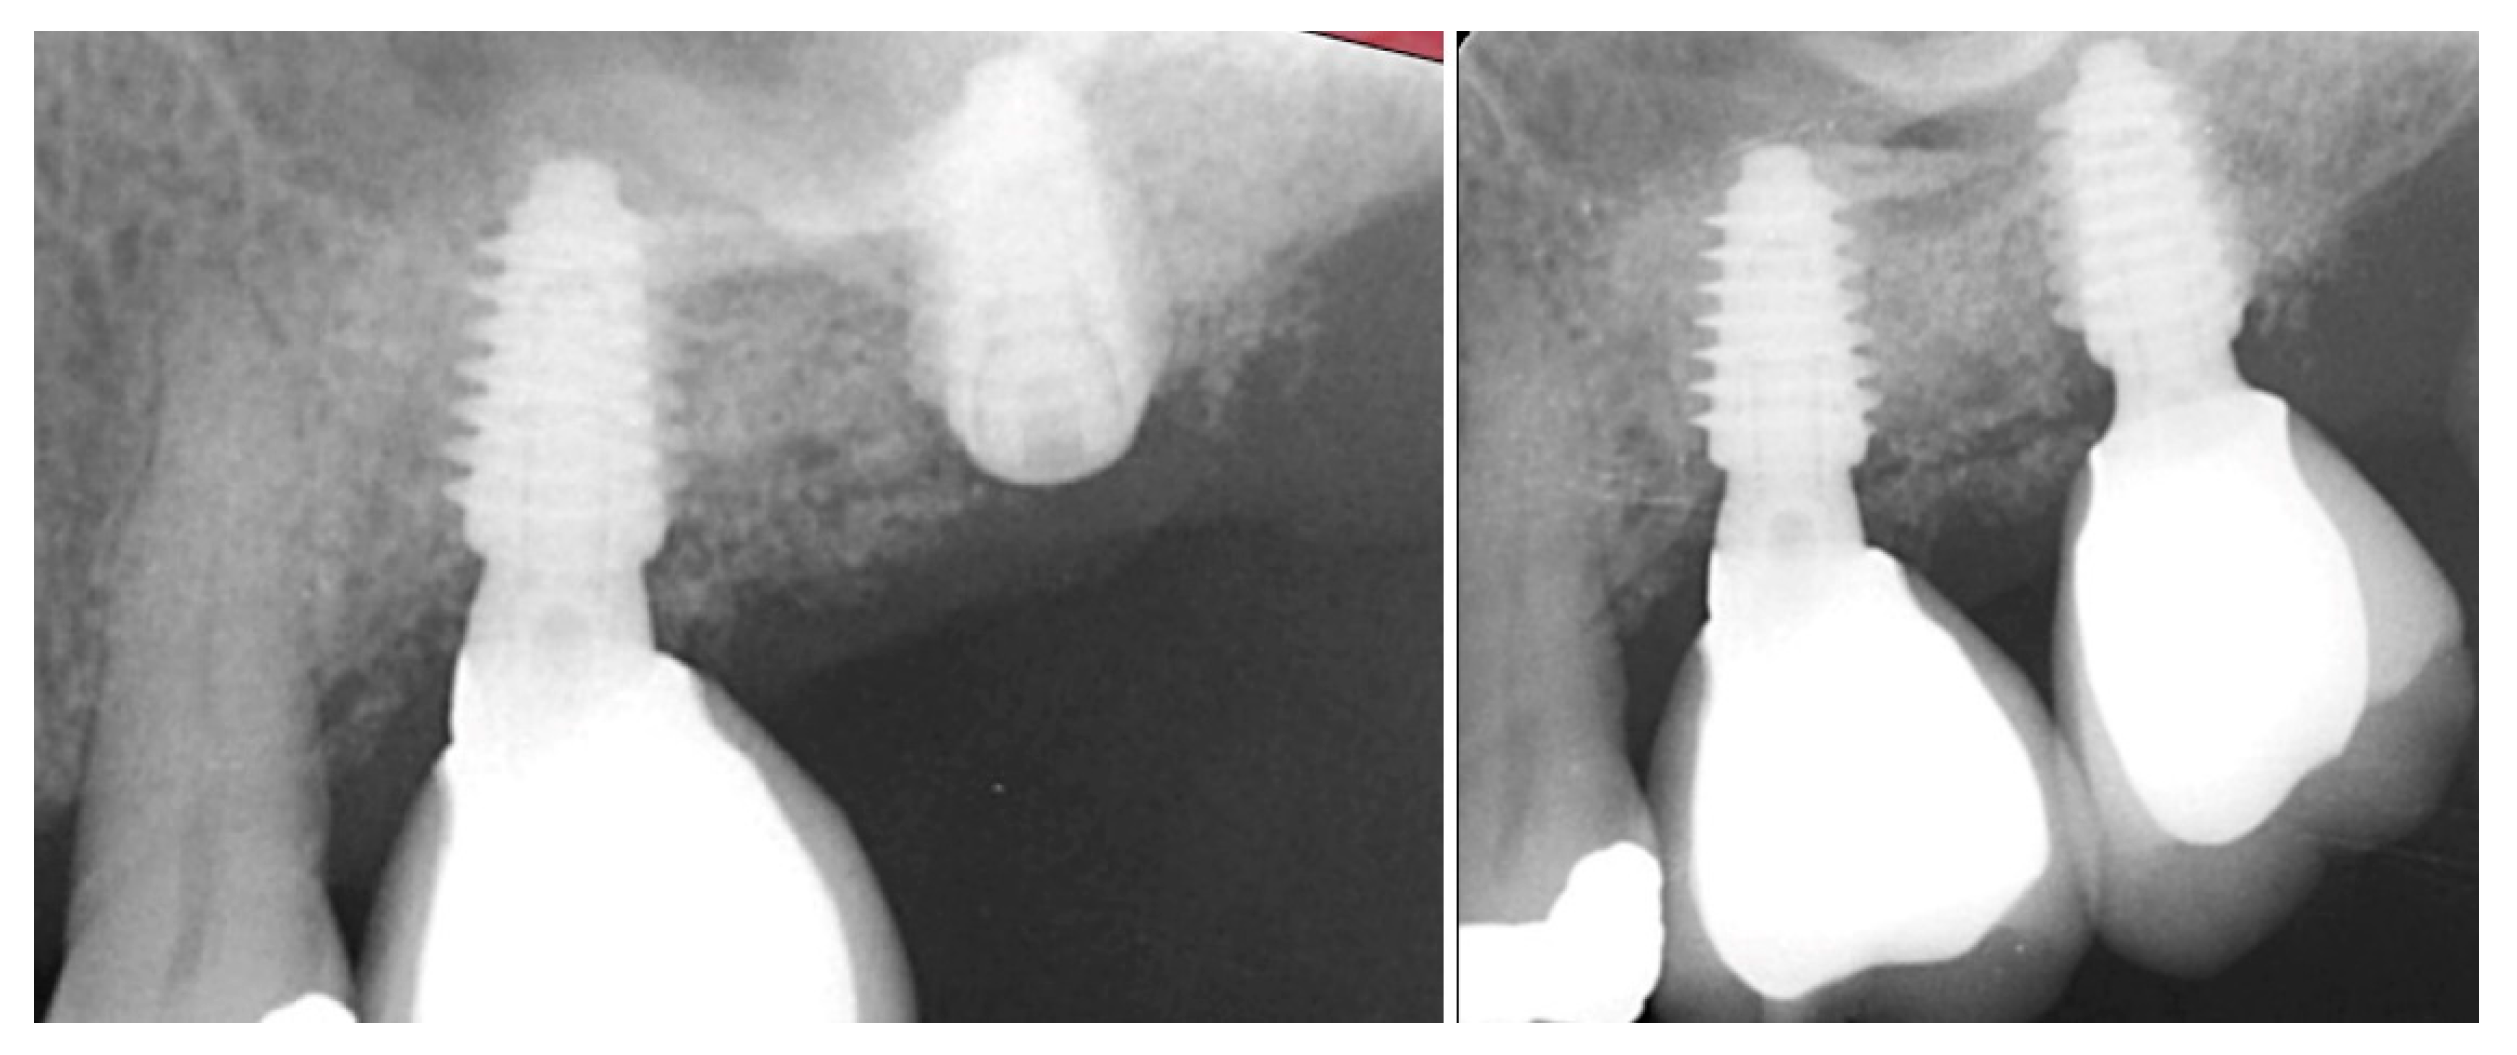

Figure 11.

Radiograph demonstrating sufficient height of the ridge to allow primary stability of an implant placed at the 2nd molar with a crestal sinus augmentation at 10 weeks of graft healing (left), site preparation for the crestal sinus augmentation (middle) and implant placement into the site (right). Green line is the measurement of the height of the bone at that point between the crest and the sinus floor.

Figure 12.

Radiograph following implant placement into the 2nd molar site with simultaneous crestal sinus augmentation.

The patient returned at 10 weeks post-2nd-implant placement and a screw-retained restoration was placed on the 1st molar and a radiograph was obtained (Figure 13, left). Impressions were obtained and the restoration on the 2nd molar was placed at a subsequent appointment. Soft tissue was healthy at placement of the restoration on the 2nd molar and no marginal inflammation was noted at either site (Figure 14, left). Soft tissue at the 1-year recall remained healthy and lacking in inflammation (Figure 14, middle). At a 2-year recall, a radiograph was obtained and bone was noted to be stable at both implants (Figure 13, right). Soft tissue at the 2-year recall remained stable and no change in marginal position was noted compared to initial restoration placement (Figure 14, right).

Figure 13.

Radiograph at 10 weeks implant integration at the 2nd molar (left) and two years following restoration of the implant at the 2nd molar showing the improved vertical regeneration between the implants (right).